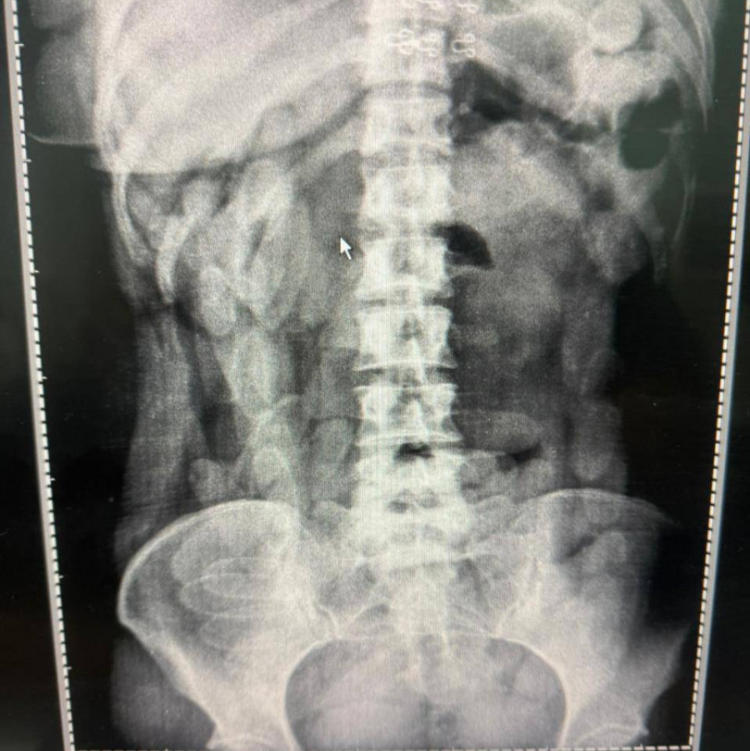

Posteriormente, las ciudadanas fueron llevadas a un centro de salud local para la realización de estudios radiográficos, donde se detectaron cuerpos extraños con forma de cápsulas en la cavidad abdominal de ambas.

Ante ese resultado, fueron derivadas a un hospital, donde permanecieron internadas con custodia hasta completar el proceso de evacuación. Como resultado, las involucradas expulsaron un total de 156 cápsulas con cocaína, arrojando un peso final de 1 kilo 884 gramos, según las pruebas de campo Narcotest.